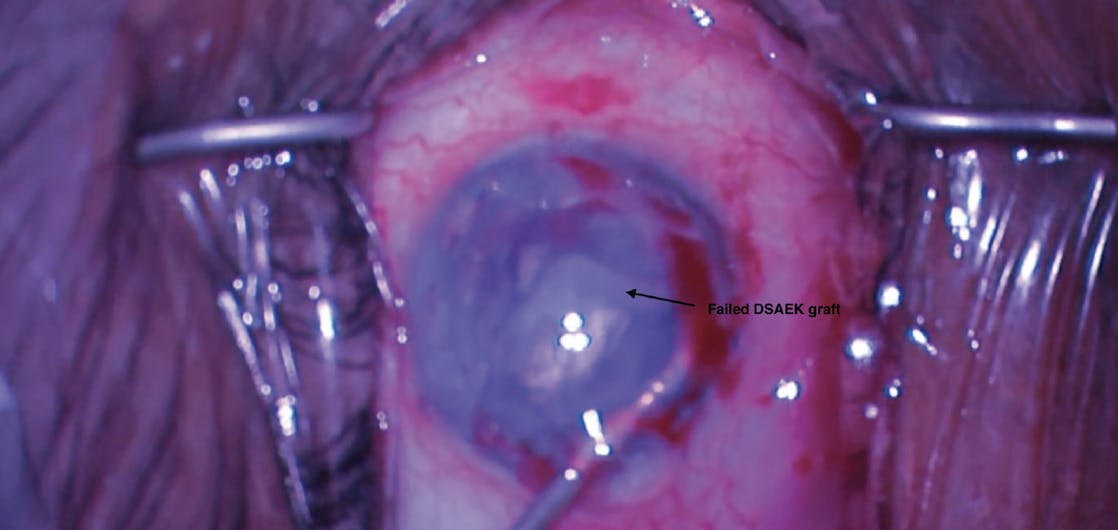

During surgery, it was noted that the failed graft was attached 360° to the iris by fibrotic tissue. In an attempt to remove it, MST retina microforceps and scissors were used to hold the graft and cut the fibrotic membrane adherences to the iris, but this maneuver was unsuccessful. Then, 23-gauge curved retina scissors were used with success to remove the fibrotic membrane adherences attaching the graft to the iris (Figure 1). An Endoserter injector (CorneaGen) was used to deploy tissue into the anterior chamber with caution, owing to significant iris atrophy. The tissue was unfolded and centralized with the help of a Sinskey hook. A 20% SF6 gas bubble was injected under the graft. The full gas bubble could not be maintained despite closing all incisions. Therefore, a 30-gauge needle was used to inject gas into the anterior chamber (Figure 2). A medium-sized gas bubble was held inside the anterior chamber, and IOP was within normal range.

<p>Figure 1. The fibrotic membrane adherences attaching the graft to the iris were removed using 23-gauge curved retina scissors.</p>

Figure 1. The fibrotic membrane adherences attaching the graft to the iris were removed using 23-gauge curved retina scissors.